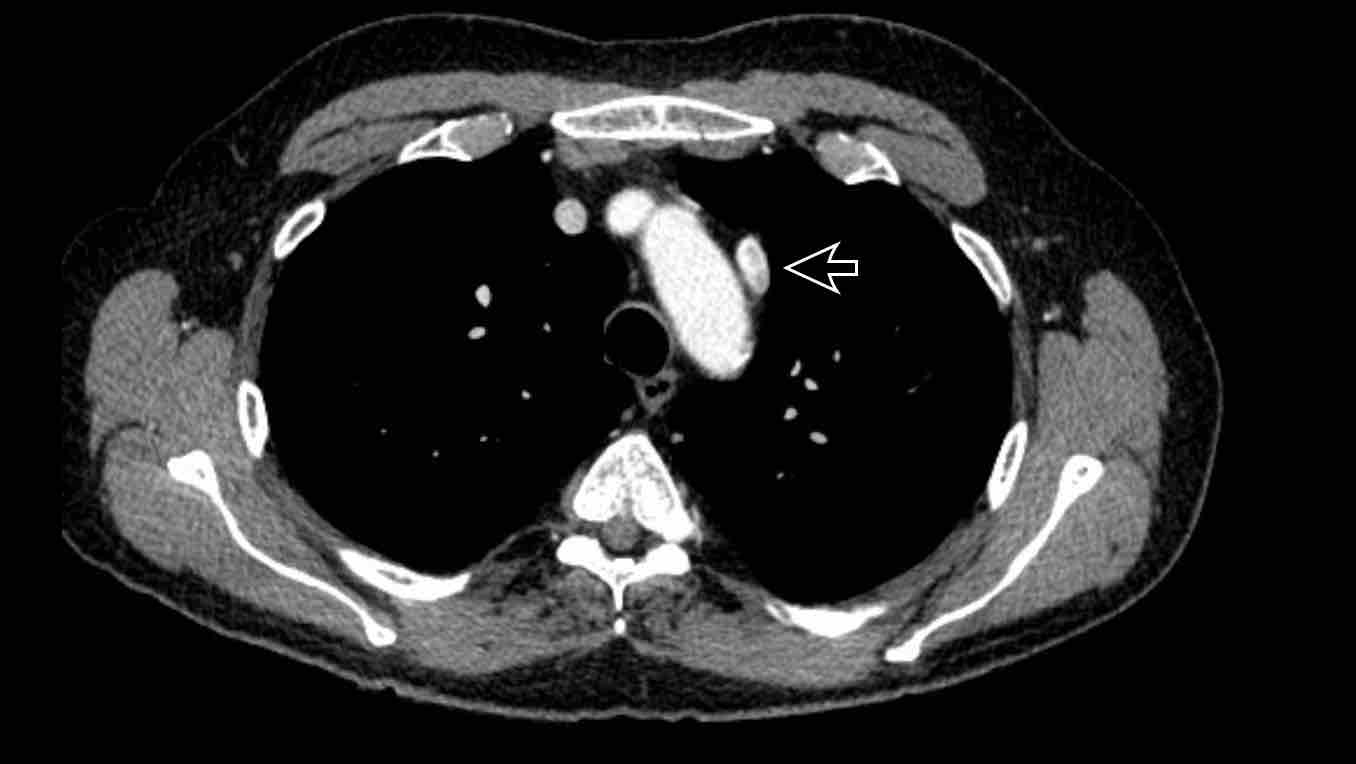

Hình ảnh

Bệnh nhân này được lên kế hoạch cắt thùy trên phải do ung thư phổi và bất thường mạch máu này ban đầu đã bị bỏ sót trên hình ảnh CT.

Những hệ quả trong phẫu thuật của bất thường như vậy nhấn mạnh tầm quan trọng của việc không bỏ sót các biến thể này.

Cuộn qua các hình ảnh.

PAPVR bên trái phát hiện tình cờ với dẫn lưu trên tim của máu từ thùy trên trái vào tĩnh mạch tay đầu trái (các mũi tên).